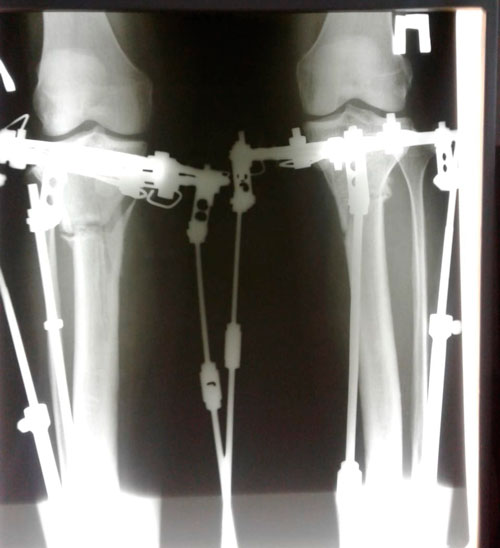

Исходник - 46 лет.

Дата операции 22.06.2018г.